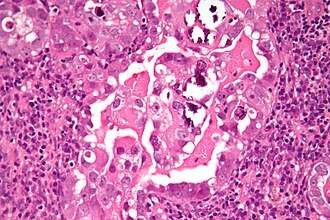

Serous carcinoma of the endometrium. H&E stain. | |

Features - serous:

- Architecture - classically papillary.

- May be glomeruloid, tubulocystic, solid (uncommon).

- Cytology:

- Columnar or cuboidal cells.

- Moderate to marked nuclear pleomorphism - variation of size, shape and staining.

- Large nuclear size variation between cells often esp. prominent.

- Singular prominent, classically red, nucleolus.

- +/-Psammoma bodies.